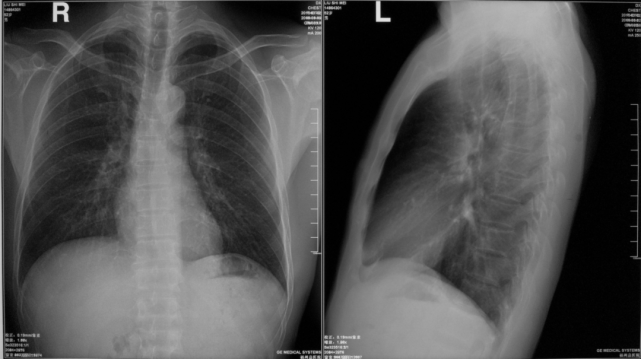

右肺下叶后基底段大叶性炎症

图片

胸部正侧位片:右肺下叶见片状致密影,右侧膈面及邻近胸廓边缘模糊(箭头所示),心缘清楚